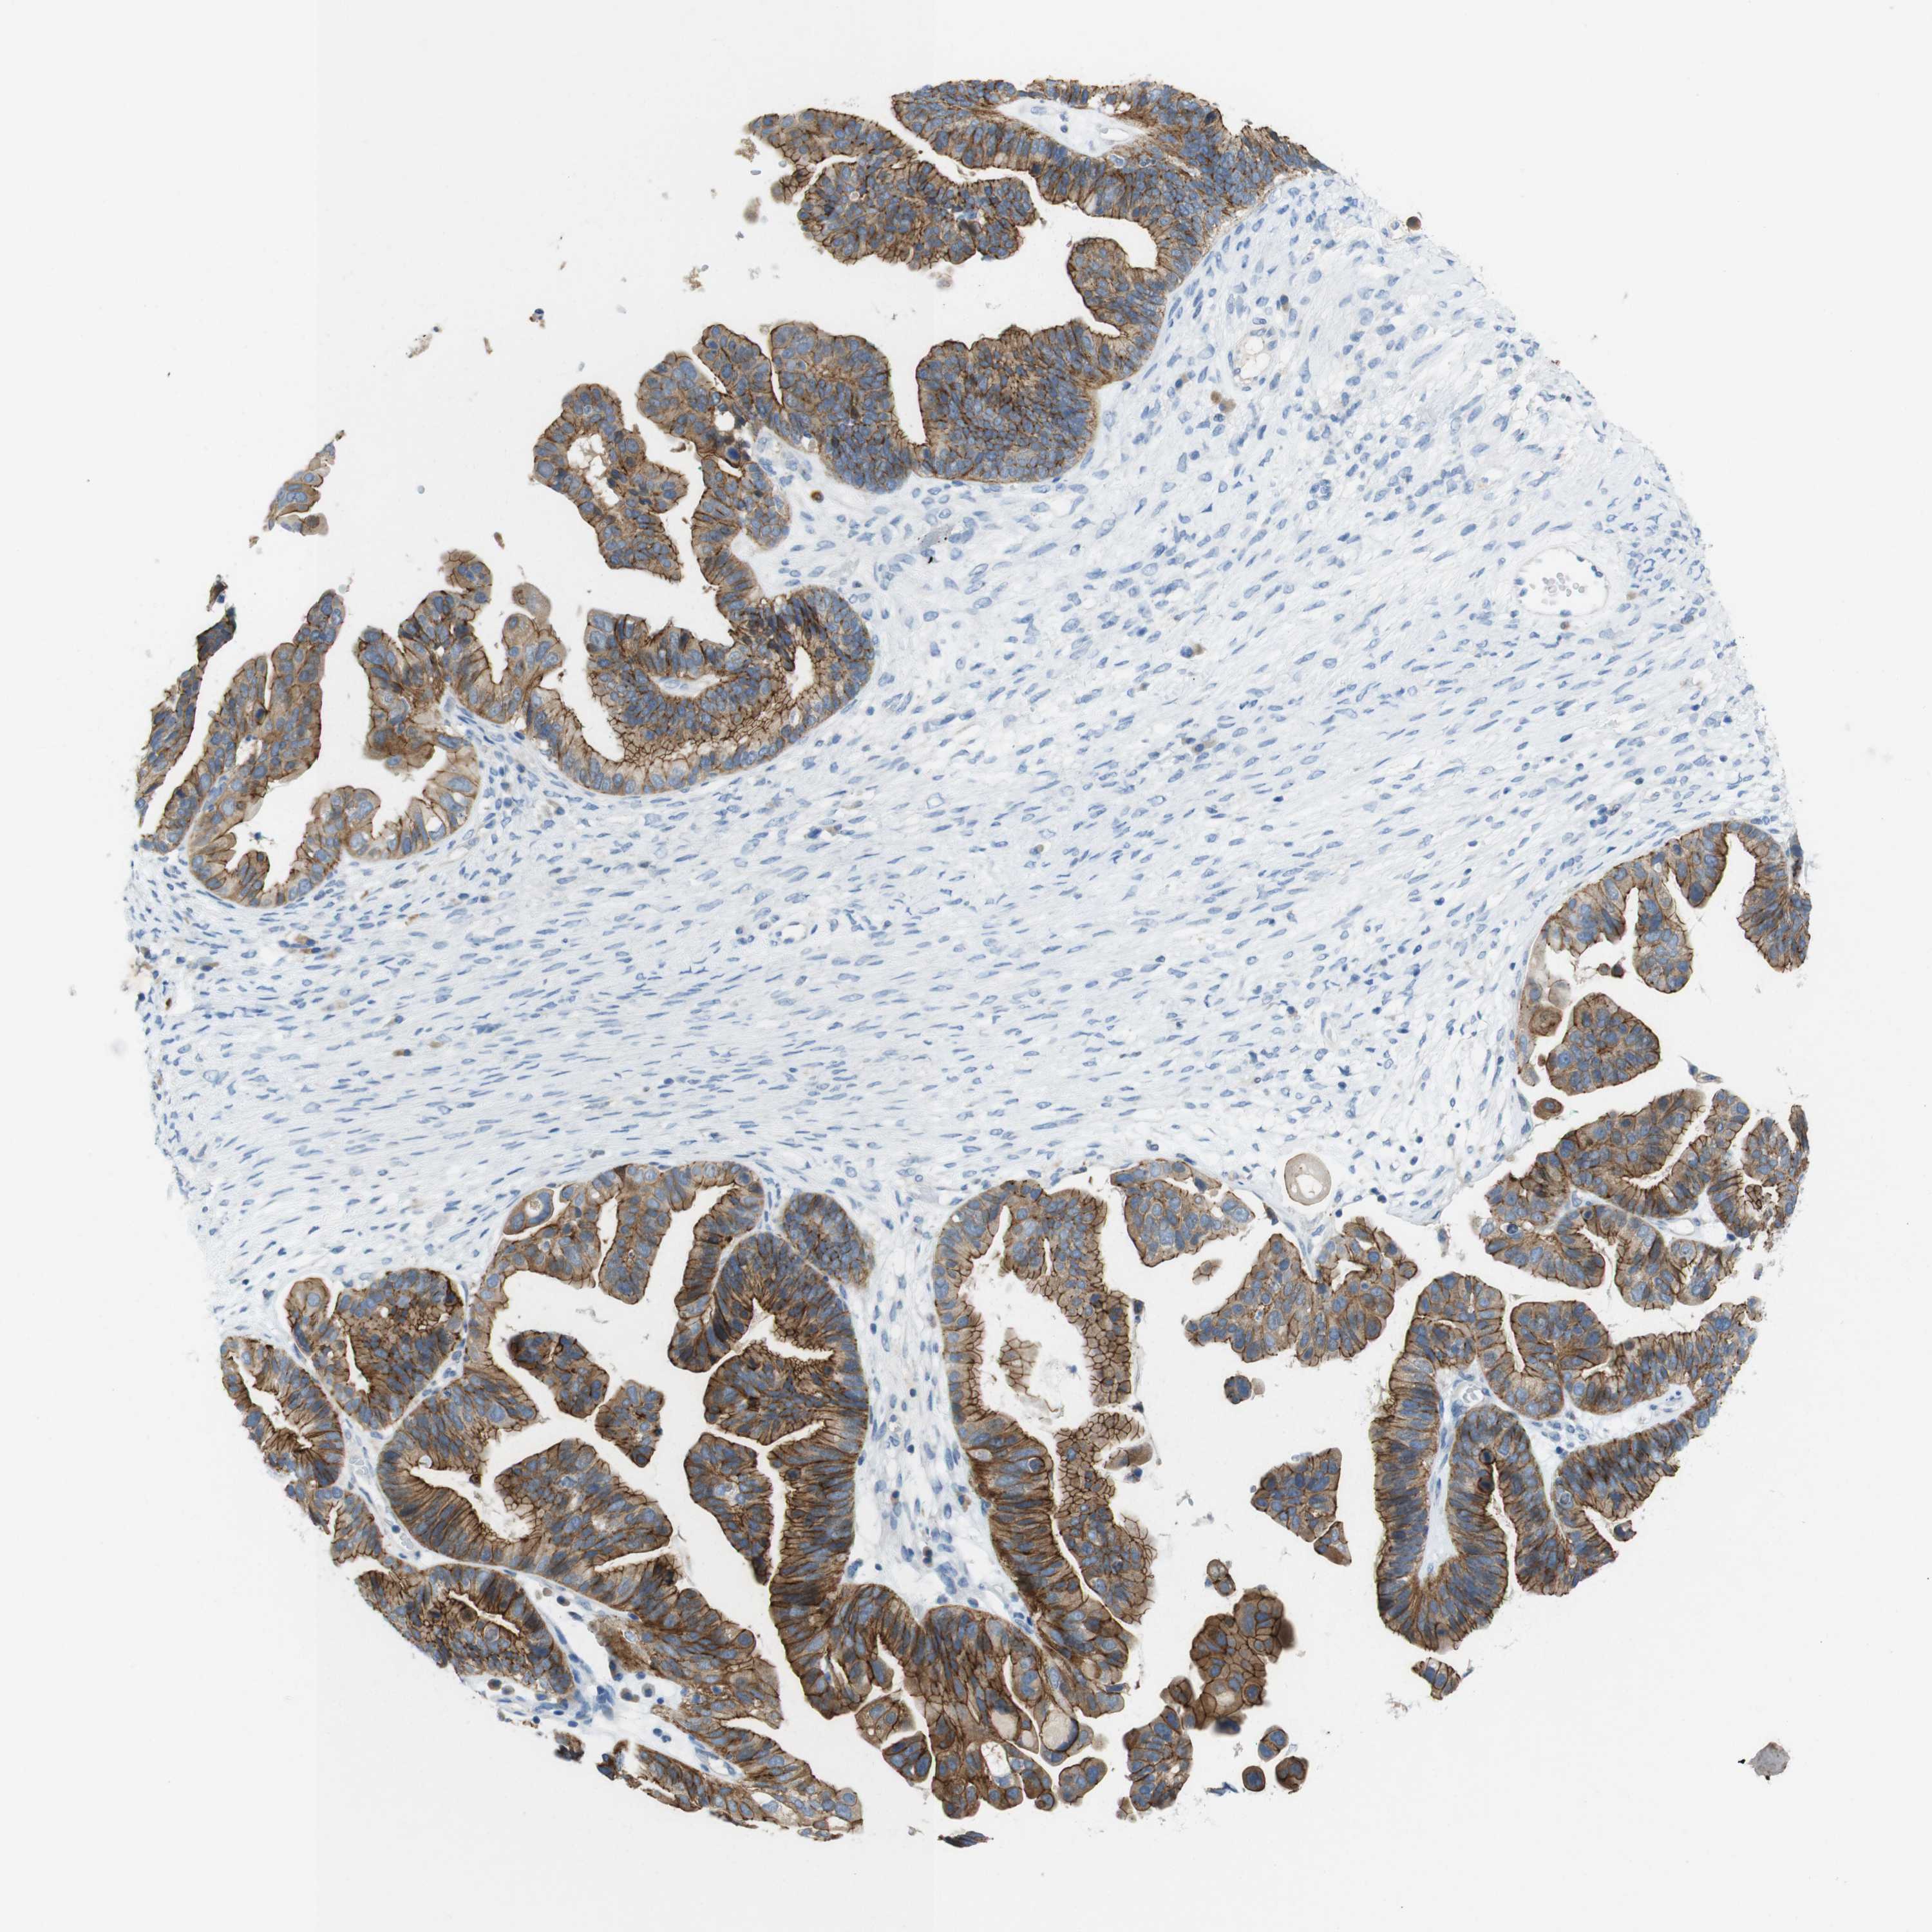

OVARIAN CANCER - Protein expressioni

A mouse-over function shows sample information and annotation data. Click on an image to view it in a full screen mode. Samples can be filtered based on level of antibody staining by selecting one or several of the following categories: high, medium, low and not detected. The assay and annotation is described here.

Note that samples used for immunohistochemistry by the Human Protein Atlas do not correspond to samples in the TCGA dataset.

Antibody stainingi

Antibody staining in the annotated cell types in the current human tissue is reported as not detected, low, medium, or high, based on conventional immunohistochemistry profiling in selected tissues. This score is based on the combination of the staining intensity and fraction of stained cells.

Each image is clickable and will lead to virtual microscopy that enables deeper exploration of all samples and also displays staining intensity scores, fraction scores and subcellular localization as well as patient and tissue information for each sample.

Antibody HPA053337

Antibody CAB013244

Staining

High

Medium

Low

Not detected

Intensity

Strong

Moderate

Weak

Negative

Quantity

>75%

75%-25%

<25%

None

Location

Nuclear

Cytoplasmic/membranous

Cytoplasmic/membranous,nuclear

Cystadenocarcinoma, serous, NOS

Cystadenocarcinoma, mucinous, NOS

Carcinoma, endometroid